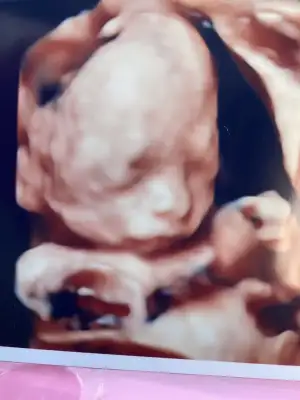

Teyzeleri çok şükür her şey yolunda minnak bir Pera var içerde. Sadece bu sefer de üç gün geri çıktı ona çok takıldım ama tabiki çok normal olduğunu biliyorum. Plasentası, suyu, rahim uzunluğu da iyi 🧿 sanırım annesine benziyor ❤️

Ay maşşaallah ya. Burnu ne kadar da belirgin. Sana mı benziyor yoksa.